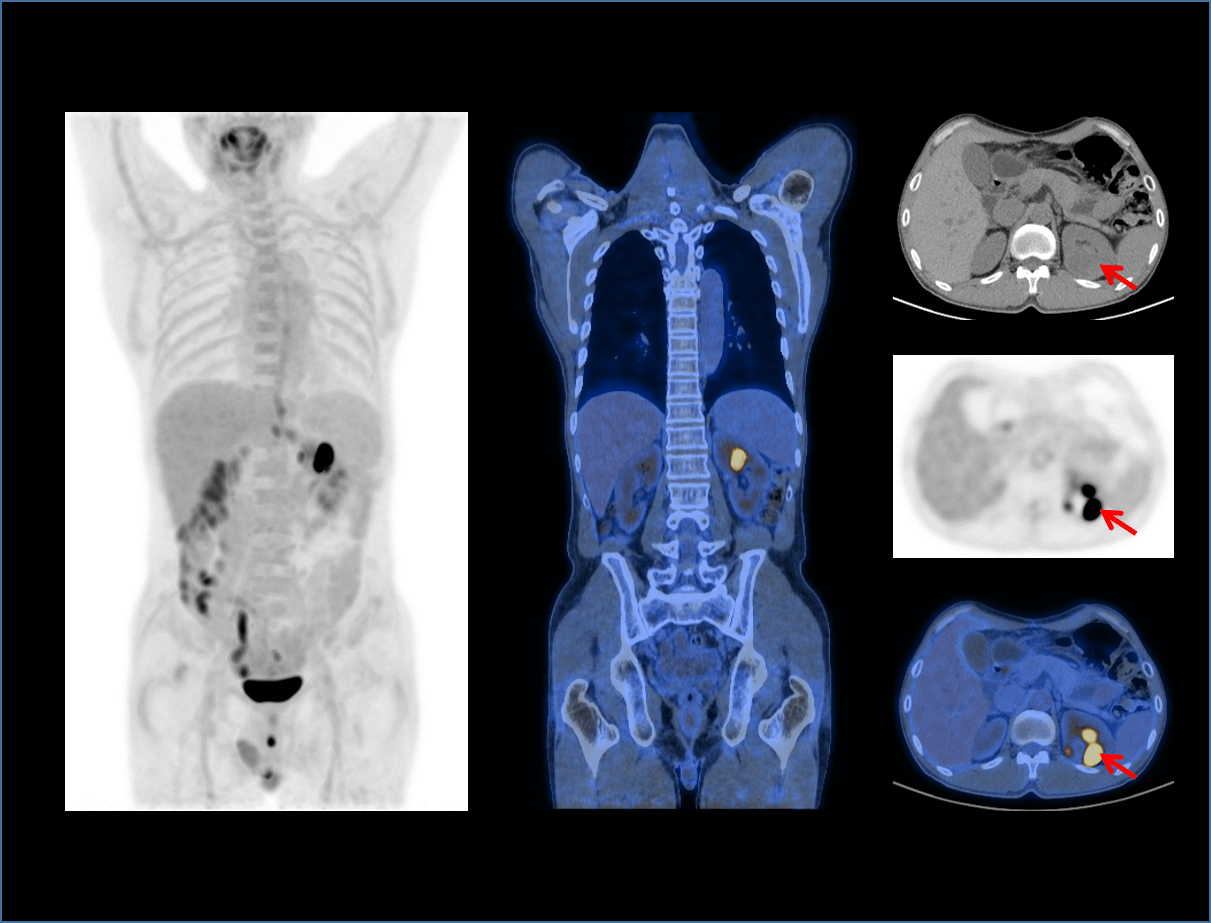

全真数字PET与160层北斗CT强强联手,将高品质的功能影像与解剖学影像精准融合,显著提升微小病灶检测精度,全面助力肿瘤、心脏和神经等重大疾病领域的精准诊疗。

24cm大轴向视野

拓展临床丰富应用

4床位全身覆盖

扫描速度成倍提升

全身快速扫描

有效提升临床效能